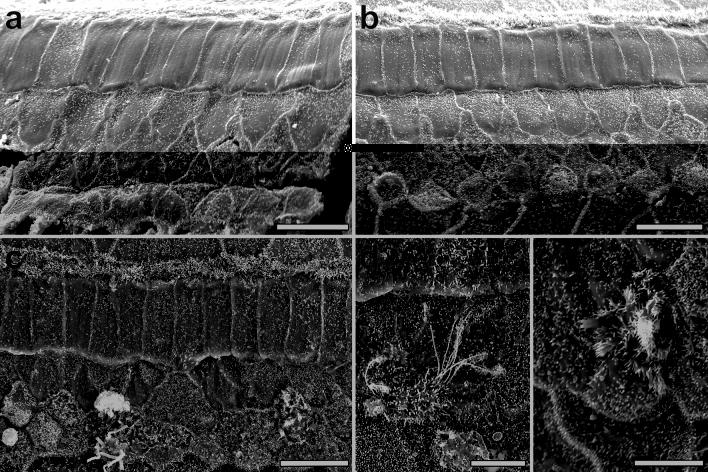

Mature mammalian cochlear hair cells (HCs) do not spontaneously regenerate once lost, leading to life-long hearing deficits. Attempts to induce HC regeneration in adult mammals have used over-expression of the HC-specific transcription factor Atoh1, but to date this approach has yielded low and variable efficiency of HC production. Gfi1 is a transcription factor important for HC development and survival. We evaluated the combinatorial effects of Atoh1 and Gfi1 over-expression on HC regeneration using gene transfer methods in neonatal cochlear explants, and in vivo in adult mice. Adenoviral over-expression of Atoh1 and Gfi1 in cultured neonatal cochlear explants resulted in numerous ectopic HC-like cells (HCLCs), with significantly more cells in Atoh1 + Gfi1 cultures than Atoh1 alone. In vitro, ectopic HCLCs emerged in regions medial to inner HCs as well as in the stria vascularis. In vivo experiments were performed in mature Pou4f3 mice in which HCs were completely and specifically ablated by administration of diphtheria toxin. Adenoviral expression of Atoh1 or Atoh1 + Gfi1 in cochlear supporting cells induced appearance of HCLCs, with Atoh1 + Gfi1 expression leading to 6.2-fold increase of new HCLCs after 4 weeks compared to Atoh1 alone. New HCLCs were detected throughout the cochlea, exhibited immature stereocilia and survived for at least 8 weeks. Combinatorial Atoh1 and Gfi1 induction is thus a promising strategy to promote HC regeneration in the mature mammalian cochlea.